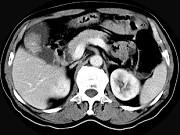

问题 男,45岁,右季肋区疼痛,Murphy征阳性,B超提示胆囊息肉,CT所见如图,最可能的诊断是()

选项 A.胆囊息肉 B.胆囊癌 C.慢性胆囊炎 D.胆囊转移癌 E.胆囊腺肌增生症

答案 B